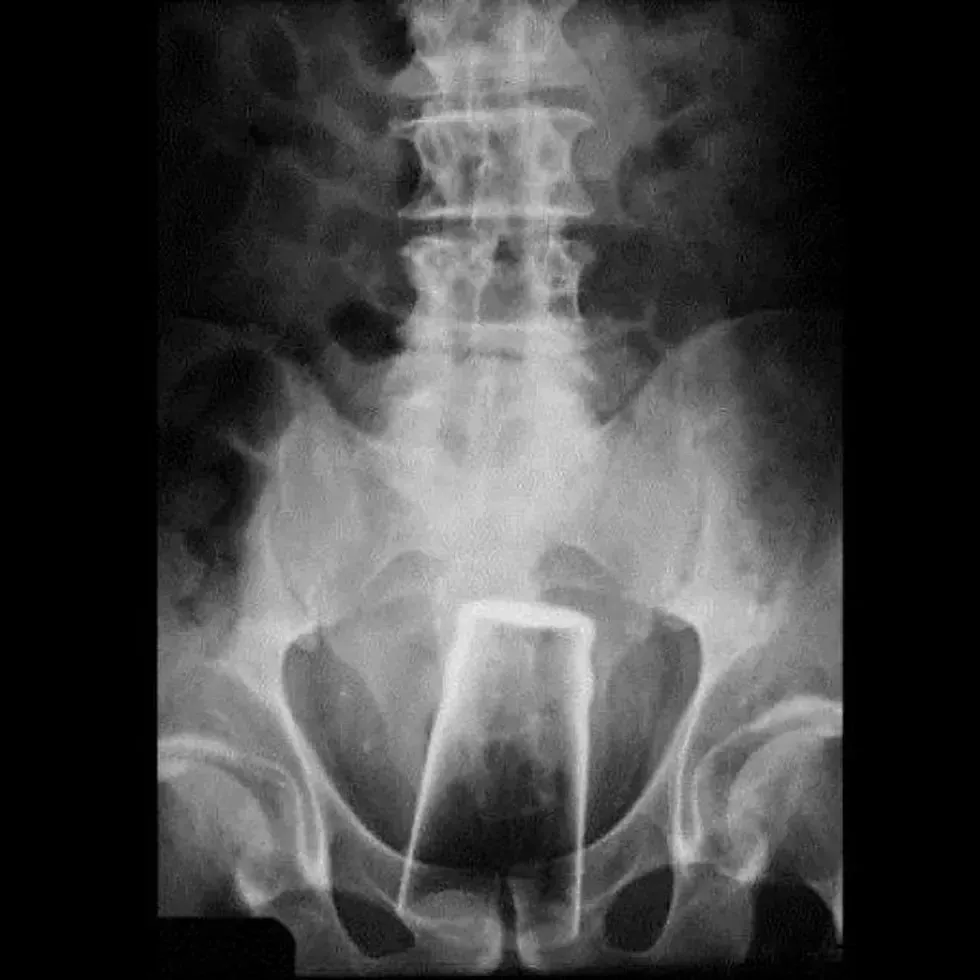

7. A lid